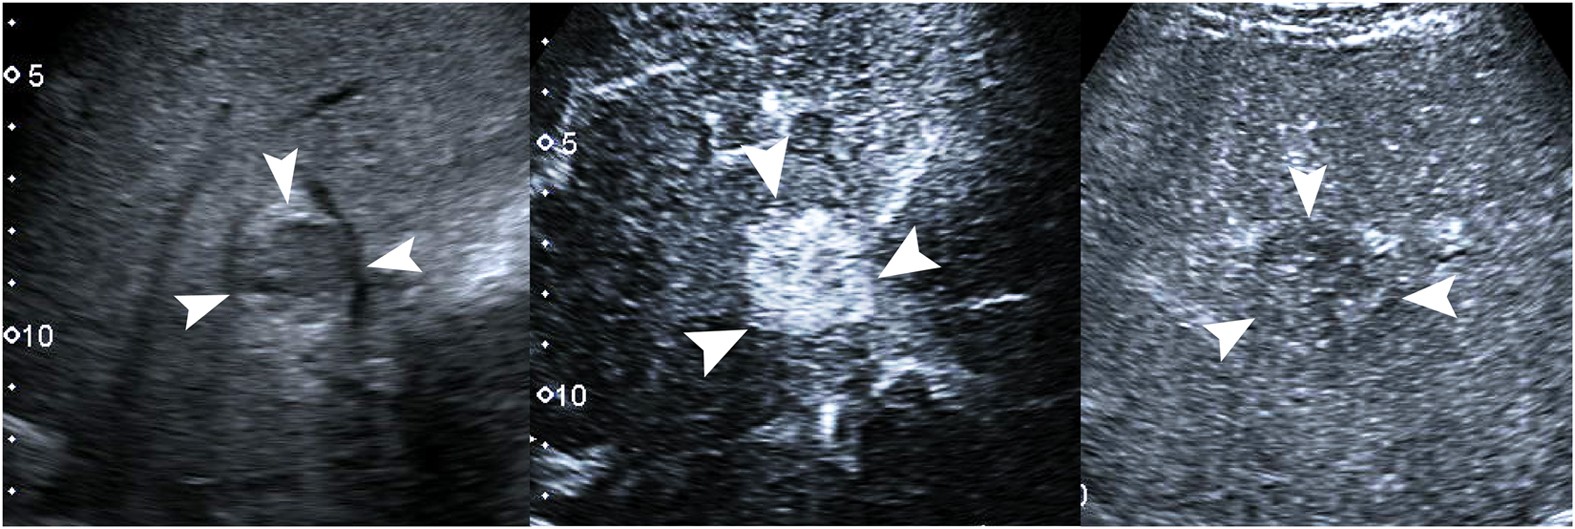

Figure 5

Hepatocellular carcinoma in a 74-year-old man.

(a) A 2.9-cm lesion (arrows) in the liver shows hypoechogenicity on conventional ultrasound. (b) Contrast- enhanced ultrasound shows hyperenhancing (arrow) in the lesion 32ās after contrast agent administration. (c) The lesion (arrows) shows hypoenhancement in comparison with adjacent liver tissue 139ās after contrast agent administration.